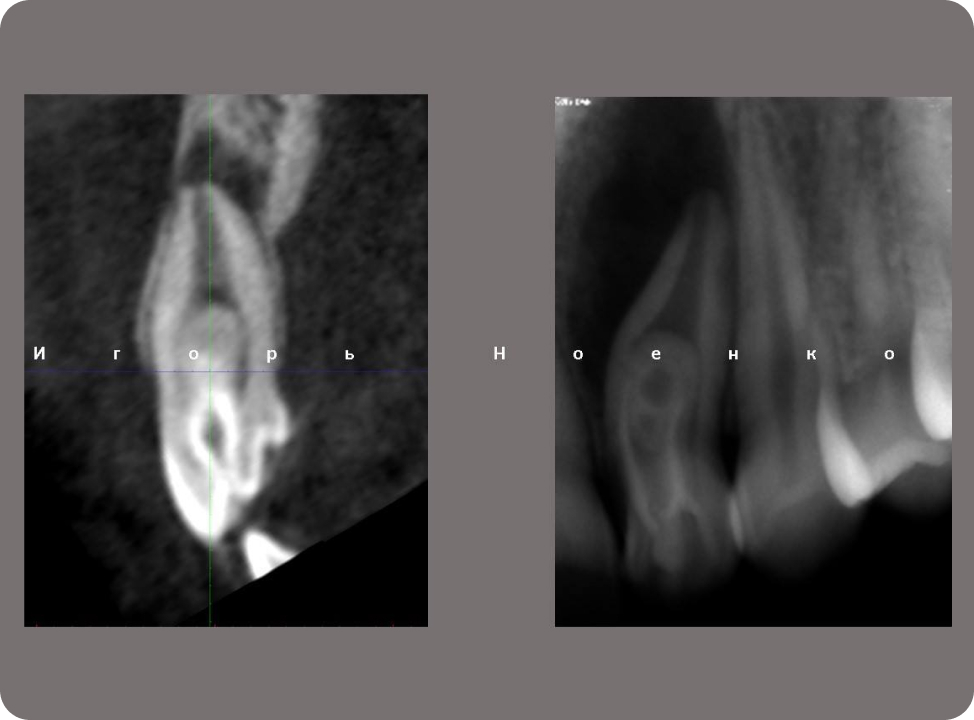

Нестандартна анатомія

Облітерації Атипове розташування каналів.

Складна анатомія. Облітерації-причини.

Сі шейп канали, класифікація та особливості обробки в молярах та премолярах.

Ігор Ноєнко

"Нестандартна анатомія"